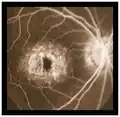

- Angiografía con fluoresceina: muestra una coroides oscura debido a depósitos de lipofuscina dentro del epitelio pigmentario de la retina e hiperfluorescencia macular debido al efecto ventana.